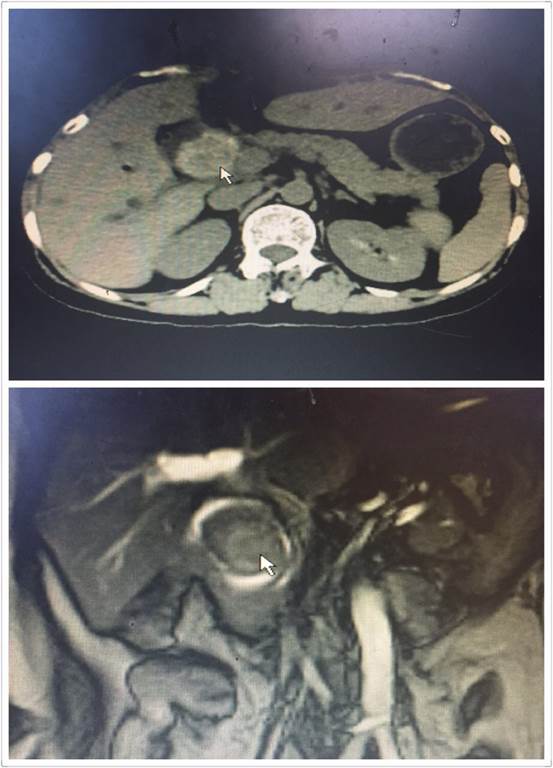

腹腔鏡手術(shù)雖好,但是對于有腹部多次手術(shù)史、腹腔廣泛粘連的患者來說,由于腹腔解剖結(jié)構(gòu)改變,腹腔鏡手術(shù)倒變成了雷區(qū)。近日,肝膽外科收住了一位老年患者,進院時已出現(xiàn)了腹痛、發(fā)熱、黃疸。進一步檢查后顯示,患者膽總管結(jié)石阻塞膽管,膽道擴張,肝功能差,急需手術(shù)治療(見圖1)。然而這位患者似乎有些“命途多舛”,在這之前她就曾因膽管結(jié)石、腸梗阻在外院作了三次大手術(shù),所以腹部留下了整整長約30CM的手術(shù)疤痕(見圖2)。外院的醫(yī)生了解到該情況后建議直接“開刀”,患者通過打聽得知我院腹腔鏡技術(shù)精湛,遂慕名而來。

圖1